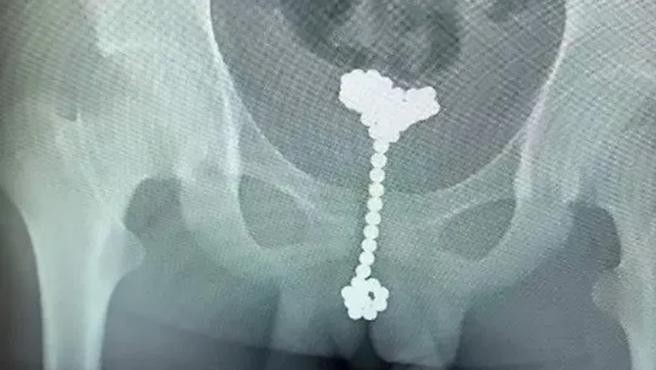

Un niño de 12 años acudió al hospital de la ciudad de Wuhan, en el centro de China, por unos fuertes pinchazos abdominales.

Tras varias preguntas del Dr. Wang Jun, el niño acabó por revelar que hacía "aproximadamente 70 días" que se introdujo un total de "31 bolas magnéticas en el interior del pene para explorar el cuerpo". Se trataba de 31 'buckyballs', unos juguetes que consisten en esferas de metal apilables de todo tipo de formas.

Las bolas pudieron ser extraídas en su totalidad tras una laboriosa actuación de los médicos. Tuvieron que bombear aire en la vejiga del menor para poder mantener cada esfera quieta y así poder recuperarlas.

Según afirma el urólogo Wang Jun, dicha práctica evitó someter al niño a una operación de mayor riesgo.